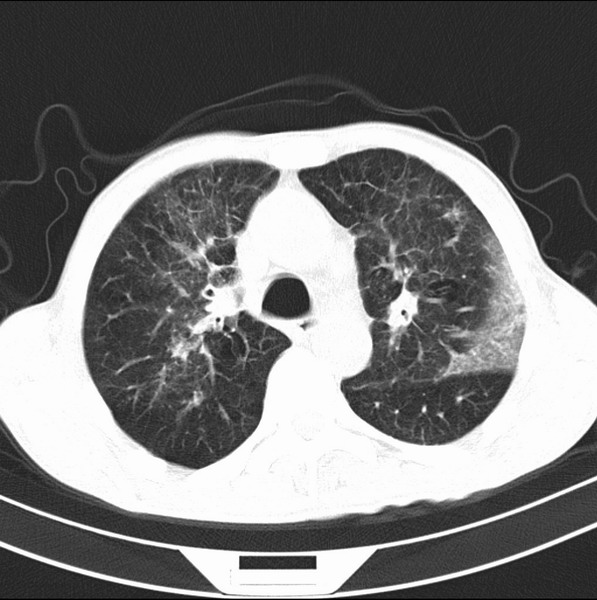

标题: CT19600:能否诊断为转移?

女、55

3年前盲肠癌、一年半前诊断膀胱癌,现在呼吸困难,临床考虑为肺转移

请问胸部ct如何诊断?能否排除淋巴管炎,纵隔窗没有问题。